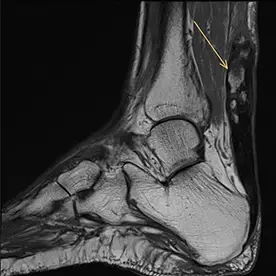

Akute Ruptur der Achillessehne mit Dehiszenz der Sehnenstümpfe um 2,4cm und gering vermehrter Flüssigkeit zwischen den Sehnenstümpfen (Bild 11-1). Zusätzlich zeigen sich Verkalkungen der Sehne als Zeichen einer chronischen Tendinosis calcarea (Bild 11-2, Pfeil).